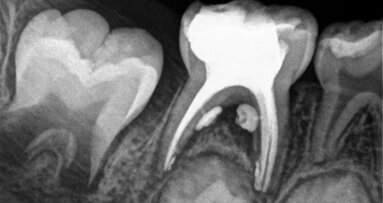

Les professeurs Mario Luis Zuolo et Arthur de Siqueira Zuolo présentent la détection clinique, le diagnostic et le traitement d’une ...

La pulpectomie est un traitement endocanalaire qui consiste à retirer le tissu pulpaire irréversiblement infecté ou nécrosé, à la suite de lésions ...